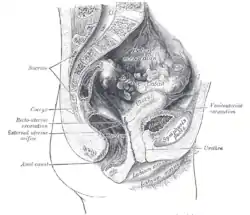

Sagittal section of the lower part of a female trunk, right segment. (Excavatio recto-uterina labeled at bottom right.) | |

The rectouterine pouch (recto-uterine pouch, pouch of Douglas, or rectovaginal pouch) is the extension of the peritoneum into the space between the posterior wall of the uterus and the rectum in the human female.[1]

In women, the rectouterine pouch is the deepest point of the peritoneal cavity. It is posterior to the uterus, and anterior to the rectum.[2] Its anterior boundary is formed by the posterior fornix of the vagina.[1] The pouch on the other side of the uterus near to the posterior fornix is the vesicouterine pouch.

After passing over the fundus of the uterus, the peritoneum extends inferiorly along the entire posterior aspect of the uterus, reaching the posterior vaginal wall before reflecting superior-ward onto the anterior aspect of the rectal ampulla (i.e. the inferior portion of the rectum).[3]